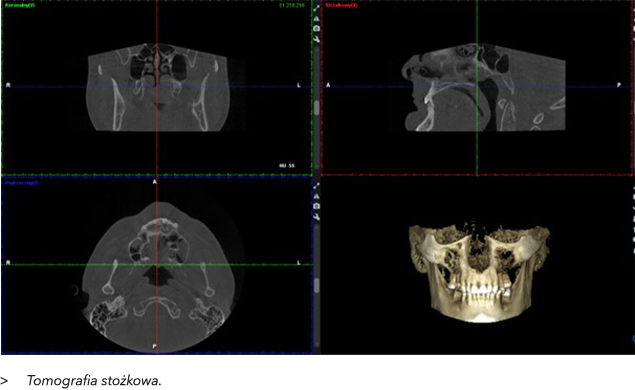

3. CBCT – Tomografia Stożkowa 3D w Ortodoncji

CBCT (Cone Beam Computed Tomography) to zaawansowana metoda obrazowania, która w ortodoncji zyskuje na popularności, oferując trójwymiarowe obrazy struktur kostnych, w tym stawów skroniowo-żuchwowych (TMJ). CBCT pozwala na dokładną ocenę stawów skroniowo-żuchwowych, które pełnią kluczową rolę w funkcjonowaniu układu żucia. Dolegliwości związane ze stawami skroniowo-żuchwowymi mogą prowadzić do bólu, trzeszczenia, ograniczenia ruchomości żuchwy, a także problemów ze zgryzem.

Korzyści z zastosowania CBCT w diagnostyce i leczeniu problemów z TMJ to:

•  Dokładna ocena strukturalna – CBCT umożliwia szczegółową wizualizację stawu skroniowo-żuchwowego w 3D, wykrywając zmiany takie jak uszkodzenia chrząstki, zwichnięcia, zmiany zwyrodnieniowe, czy zmiany w położeniu głowy kości żuchwy.

•  Ocena funkcji stawu – CBCT umożliwia monitorowanie funkcji stawu w czasie rzeczywistym, co pozwala na dokładne śledzenie jego ruchomości i wykrywanie nieprawidłowości.

•  Diagnostyka patologii – Umożliwia wykrycie wczesnych zmian patologicznych, takich jak zapalenia, co może zapobiec dalszemu rozwojowi problemów stawowych i ułatwić planowanie leczenia.

•  Planowanie leczenia – W przypadku konieczności leczenia chirurgicznego stawu skroniowo-żuchwowego, CBCT pozwala na precyzyjne zaplanowanie zabiegu. Pozwala również na monitorowanie efektów leczenia, szczególnie w ortodoncji, gdzie prawidłowe ustawienie stawów skroniowo-żuchwowych jest kluczowe dla sukcesu terapii.

•  Ocena postępu leczenia – CBCT stawów skroniowo-żuchwowych umożliwia regularne monitorowanie efektów leczenia, zarówno ortodontycznego, jak i operacyjnego, poprzez porównanie nowych obrazów z wcześniejszymi.